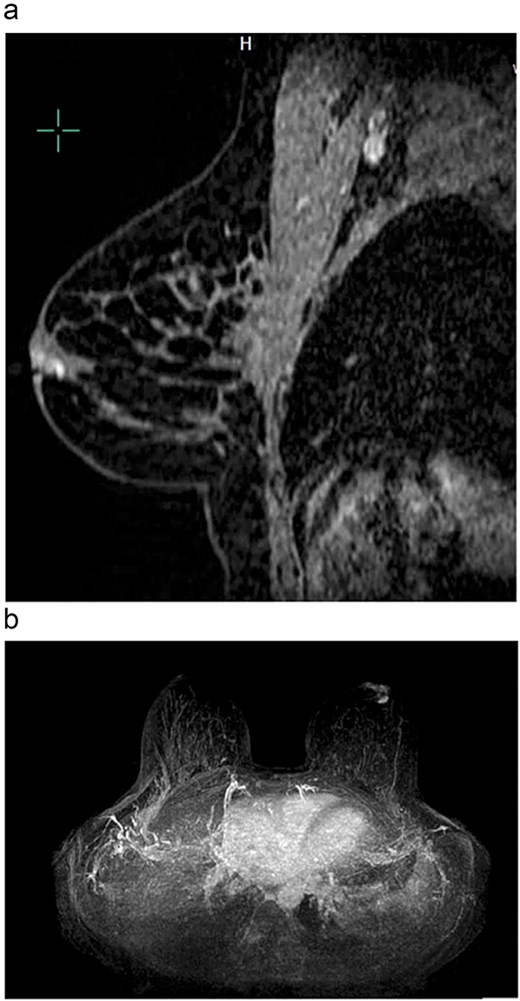

Magnetic resonance breast imaging revealed T2 enhancement surrounding the excisional biopsy cavity in the subareolar breast (Fig. 1a and b) and no suspicious internal mammary or axillary lymphadenopathy. Genetic testing did not identify any known pathogenic mutations associated with BC.

(a) Sagittal view of left breast retroareolar lesion. Enhancement appears to align in a duct in the retroareolar breast. (b) Axial view of left breast retroareolar lesion. Enhancement appears to align in a duct in the retroareolar breast.